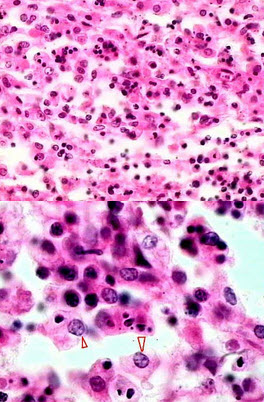

炎症病变中,主要有中性粒细胞和巨噬细胞两种吞噬细胞,其中巨噬细胞形态和名称可多种多样。

如图为肠伤寒镜下观,箭头所指吞噬了伤寒杆菌、红细胞及细胞碎片的大细胞,我们称之为()

A.伤寒细胞

B.类上皮细胞

C.异物巨细胞

D.巨噬细胞

E.泡沫细胞